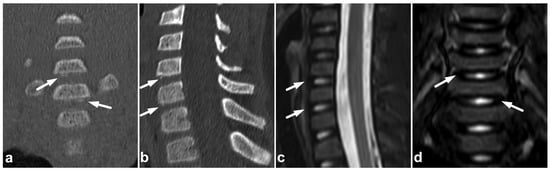

7.3. Juvenile Spondylolysis

Juvenile lumbar spondylolysis ensues from repetitive stress, but the onset of symptoms can be sudden, and the chronic pain may be exaggerated by acute trauma. The clinical presentation and the typical location of the findings centered in the pars interarticularis help to distinguish a stress injury from an acute traumatic fracture. The spondylolysis and surrounding bone marrow edema can probably be assessed with MRI [80], but the evidence of MRI’s sensitivity is not fully concurrent [81]. However, it seems that MRI’s performance can be improved with high-resolution T1-weighted sequences optimized for bony structures [82] or with a novel ultrashort time-to-echo technique [83]. An example of a lumbar spondylolysis is presented in Figure 19. Targeted small-FOV CT may be used in estimating the age, grade, and bony union rate of the spondylolysis in treatment planning and follow-up [82,83,84,85,86].

Figure 19.

(a) Sagittal right-sided off-midline STIR. (b) Sagittal right-sided off-midline T2-weighted. (c) Sagittal right-sided off-midline black bone sequence. (d) Axial T2-weighted. (e) Sagittal left-sided off-midline STIR. (f) Sagittal left-sided off-midline T2-weighted. (g) Sagittal left-sided off-midline black bone sequence. (h) Coronal STIR. A 12-year-old female with acute lower back pain when playing with friends. MRI demonstrates bilateral bone marrow edema centered in pars interarticularis (arrows). Fracture lines are also seen bilaterally in the pars (arrowheads). No spondylolisthesis is present.